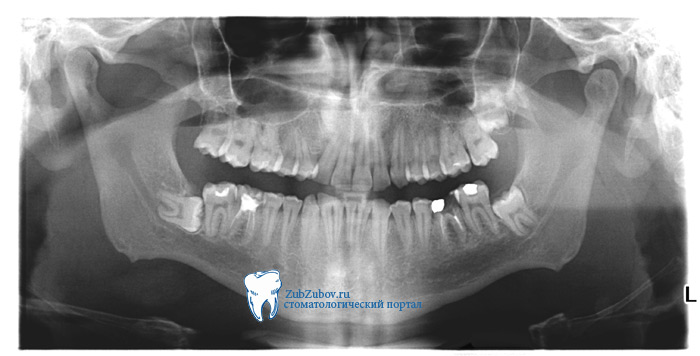

Рентген диагностики при удалении зубов мудрости

Удаление 8 зуба, без проведения качественного информативного рентгеновского обследования не рекомендуется. Даже при внешней видимости обычного зуба, восьмерка, как правило, имеет много «подводных камней». В первую очередь это искривленные корни, которые встречаются даже при нормальном расположении и росте зуба мудрости, и могут создавать трудности для его удаления, а так же стать причиной развития воспаления, так как загнутые кончики могут отламываться, оставаясь в толще кости.

Рентгеновское обследование позволяет определить количество корней зуба мудрости их строение. Соответственно при поочередном извлечении корней, скажем, элеватором, доктор будет знать, сколько всего их должно быть, и какой они формы, что является гарантией, тому, что в толще кости не останется корень или его часть.

Эффективно рентген исследование и в определении направления роста зуба мудрости. Наиболее распространенным и полноценным в отношении восьмерок является снимок выполненный на ортопантомографе. Ортопантомограф — цифровой рентген аппарат, выполняющий обзорные рентгеновские снимки ротовой полости (всех зубов).

Преимущество ортопантомограммы перед обычным прицельным снимком является в первую очередь, отсутствие влияния человеческого фактора. При проведении прицельной рентгенографии, многое зависит от того, как рентген лаборант расположит пленку в полости рта пациента. Что, в свою очередь, напрямую зависит от индивидуальных особенностей человека, а конкретно, наличия рвотного рефлекса. Чтобы произвести качественный снимок восьмого зуба, пленку нужно расположить достаточно глубоко, что, к сожалению, может вытерпеть не каждый пациент. Также, закрывание рта пациента, и как следствие сгибание пленки, неправильное ее расположение, может снизить точность в отношении направления роста и многих других показателей.

При проведении обзорной ортопантомографии, пациенту не нужно широко открывать рот, он избавлен от наличия в нем инородных предметов, что исключает возникновение рвотного рефлекса. Также, благодаря наличию лазерных датчиков, голова пациента, для проведения обследования, устанавливается абсолютно четко и правильно, и при помощи специальных держателей фиксируется, что исключает движение пациента во время съемки. Качество снимков на цифровом аппарате в разы лучше, чем на пленочном. Далее снимок обрабатывается как цифровое изображение, чем и достигается его максимальная информативность. На таком снимке гораздо лучше видны корни зуба, их количество, строение, и, конечно же, направление роста.

Панорамный снимок зубов

Таким образом, количество сведений полученных о состоянии зубов на рентгеновском снимке, делает исследование незаменимым, при удалении зубов мудрости. И если еще до посещения врача, пациент уверен в том, что вырвать зуб мудрости придется, в целях экономии времени он может пройти рентген исследование самостоятельно, и обратиться к стоматологу уже с готовым снимком на руках.

Наличие рентгеновского снимка позволяет доктору заранее просчитать ход и объем операции, подготовить необходимый инструментарий, и вычислить приблизительное время на проведение удаления.